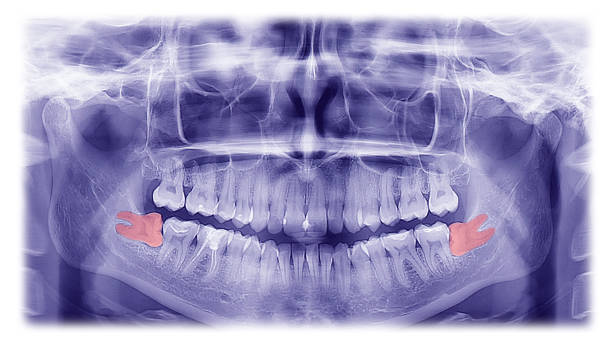

A dentist’s evaluation is a cornerstone in determining whether wisdom teeth should be removed. During a dental checkup, a comprehensive examination, including X-rays, can reveal the position, growth trajectory, and potential impact of wisdom teeth on overall dental health.

Dental professionals consider a multitude of factors during an assessment, such as the angle at which the teeth are emerging, the space available within the mouth, and the health of surrounding teeth and gum tissue. In addition, they look for signs of cysts, tumors, or decay which could influence immediate or future treatment plans. This thorough evaluation ensures that any action, whether monitoring or removal, is made with the patient’s health as the priority.